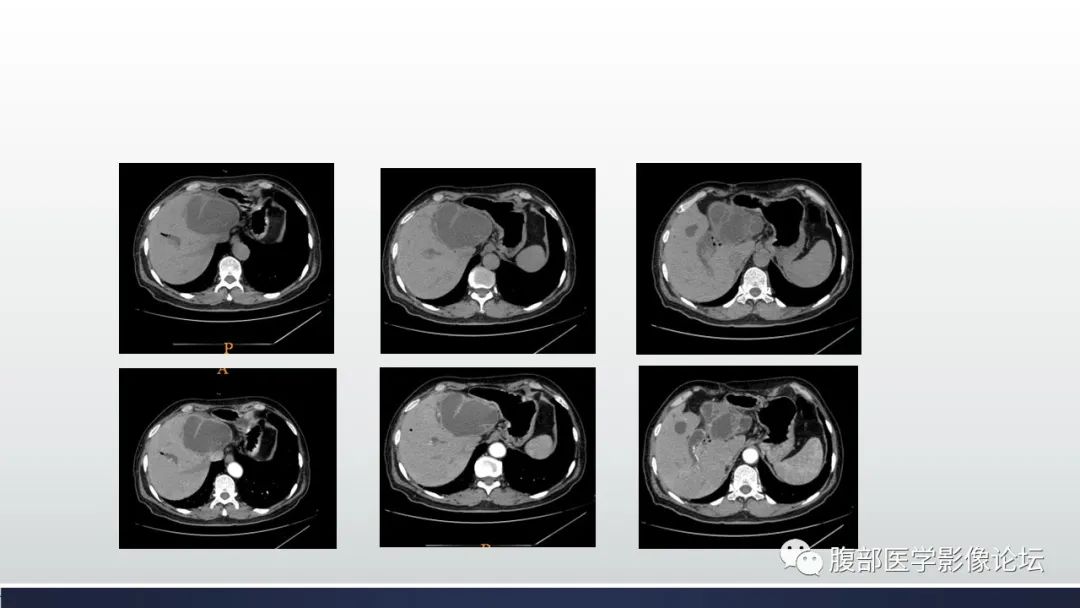

肝脏交界性粘液性囊腺瘤1例CT及MR影像

【病例】肝脏交界性粘液性囊腺瘤1例CT及MR影像-1